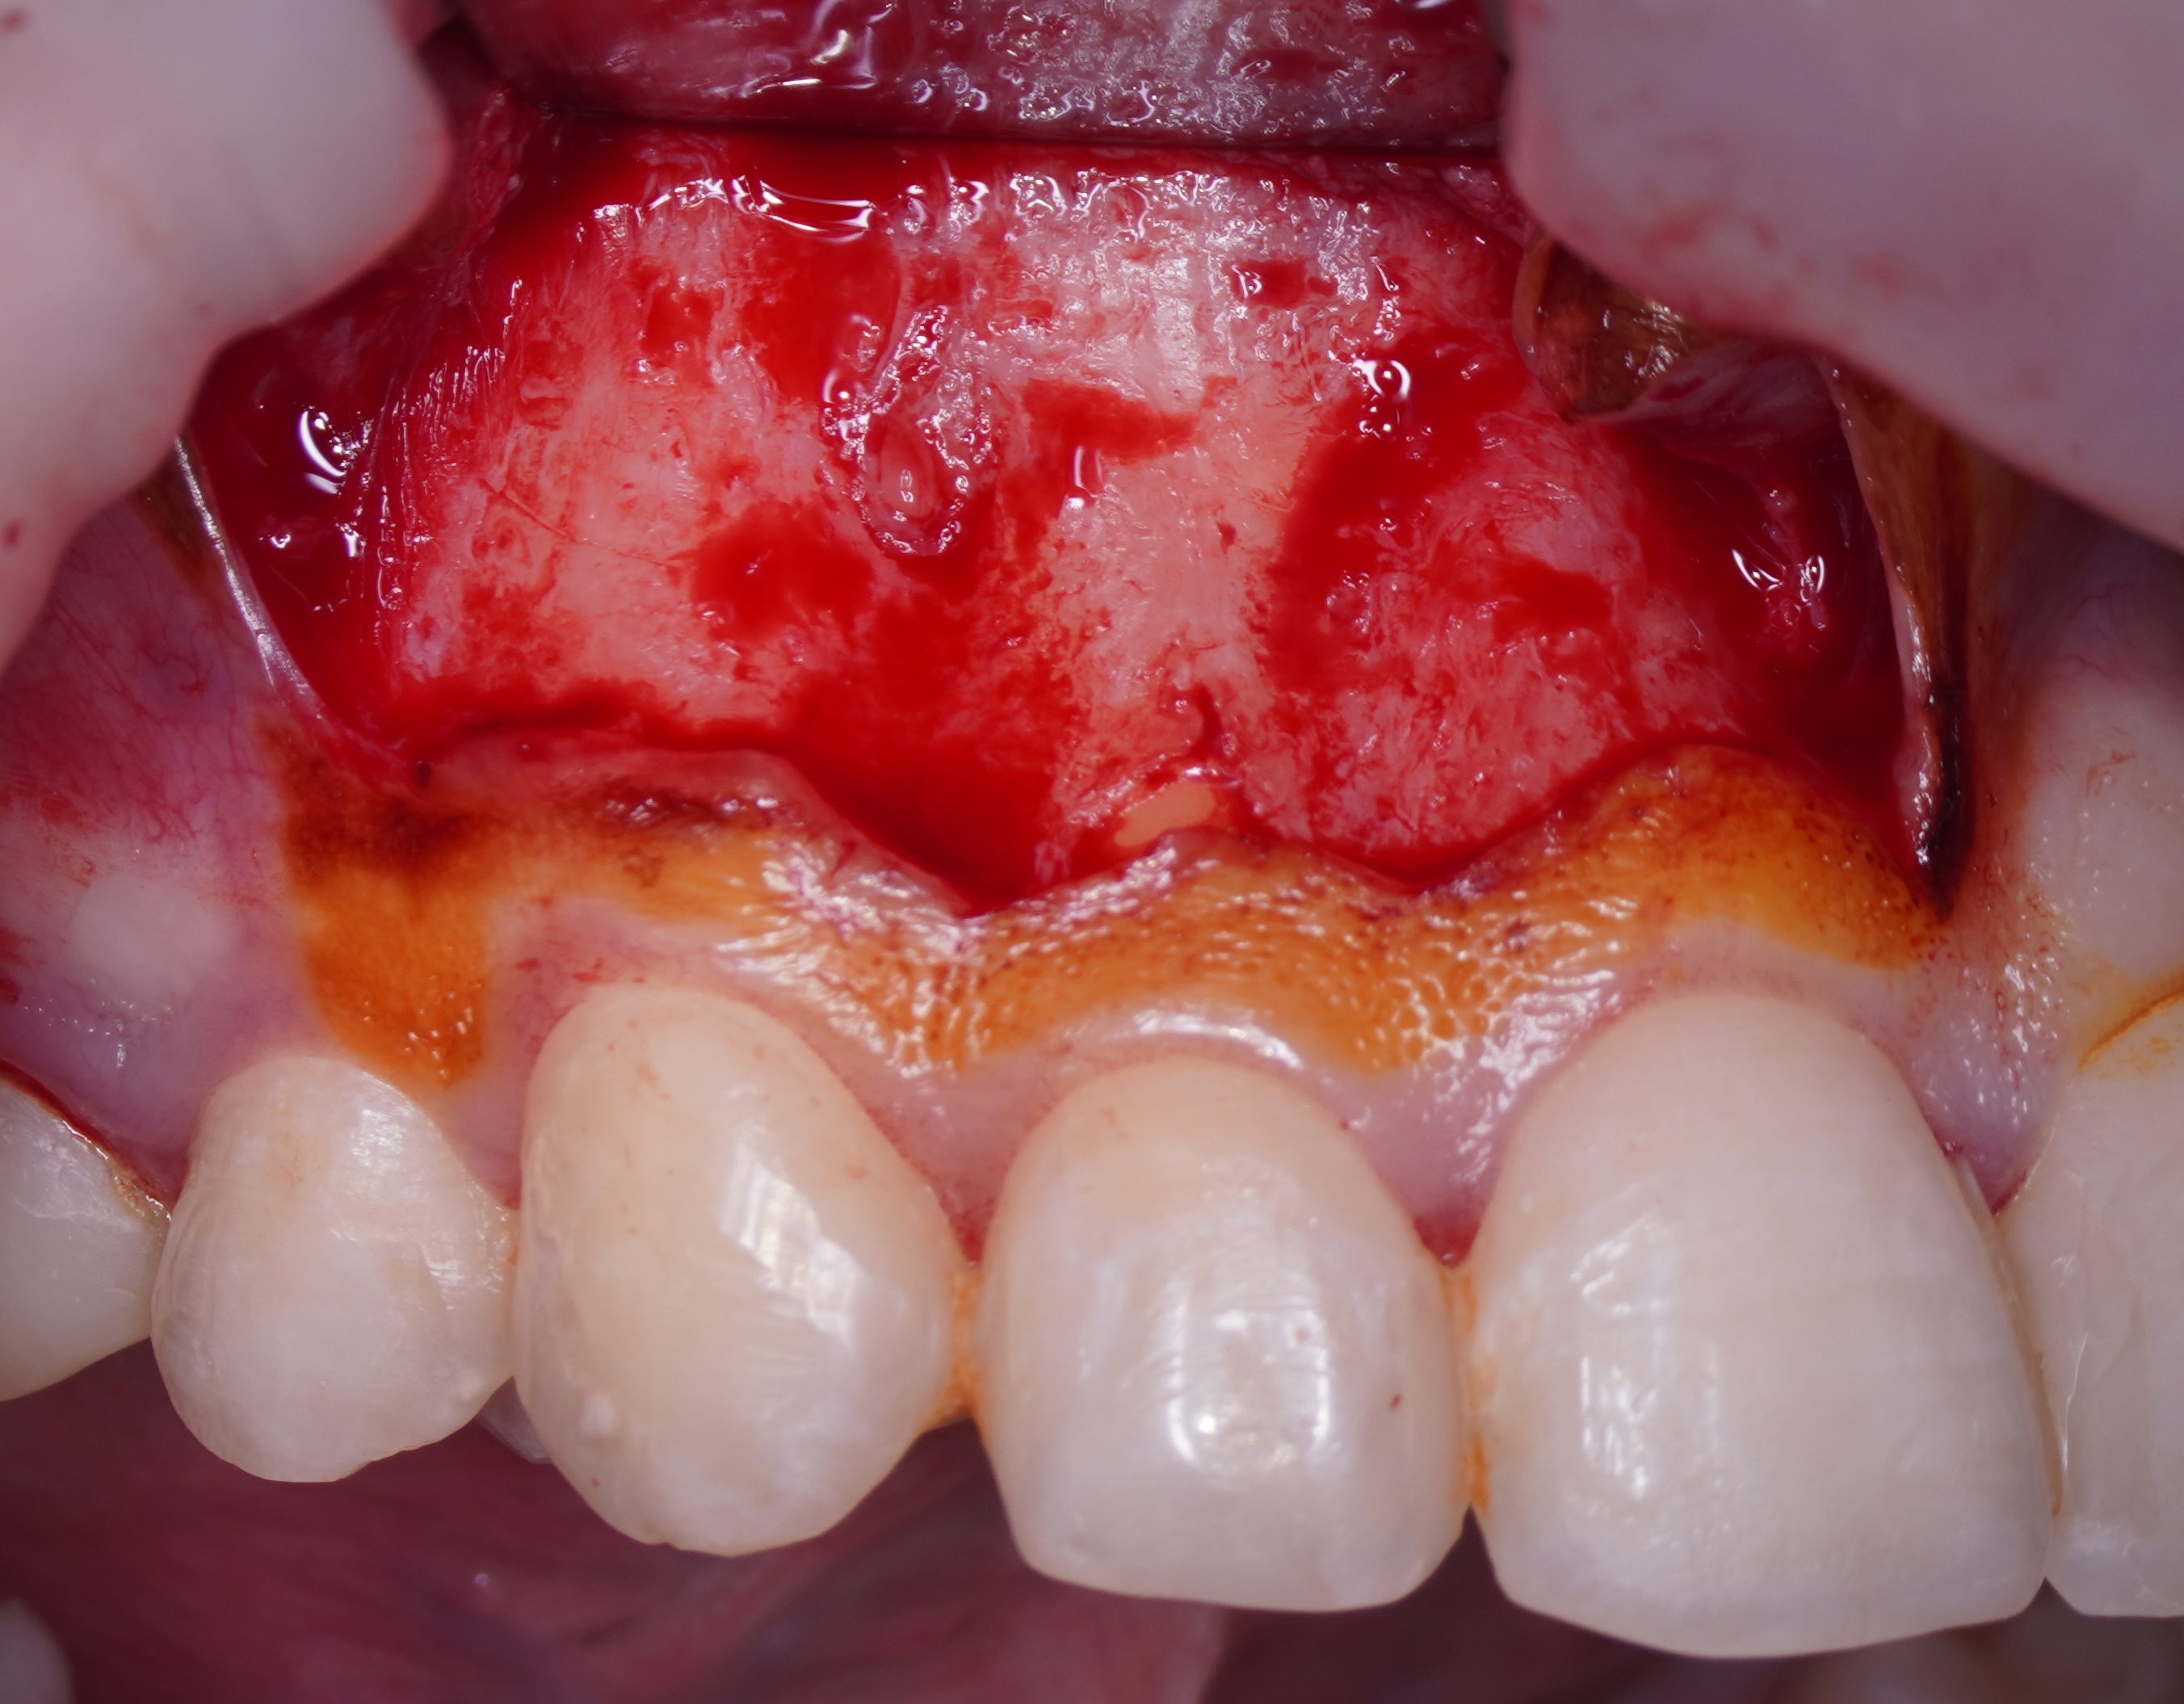

Once the apical microsurgery has been completed great care has to be taken in repositioning and suturing the elevated soft tissue. In fact, the ultimate esthetic result of the soft tissue manipulation depends on several factors such as the type of tissue, the type of incision, the choice of instruments used to incise, elevate, and retract the flap as well as careful reapproximation and a proper suture technique.

It is recommended to moisten the soft tissue with a wet gauze (sterile water or saline) before it is repositioned. The soft tissue can become dehydrated during the procedure and rehydrating it will return its natural elasticity and allows for easier reapproximation [17]. When flap shrinkage persists despite tissue rehydration, a supplementary horizontal incision may be performed at the flap base to generate a variable-thickness flap, thereby enhancing tissue adaptability and reducing contractile tension.

A good recommendation is compression of the repositioned flap with a saline-moistened piece of gauze is necessary to create a thin fibrin layer between flapped tissue and cortical bone [16].

Sutures are needed to hold the reapproximated flap in place and to allow healing of the wound by primary intention [18]. Accidental premature loss of sutures leads to delayed healing by secondary intention [19]. Bacterial colonization is an important factor leading to tissue reactions to intraoral sutures [20-24]. According to some authors [5, 10, 25, 26], monofilament synthetic sutures (polyamide, nylon) are the least traumatic, allow less bacterial migration, and are the materials of choice. The single knot, interrupted suture is used when a submarginal flap has been incised. The single knot suture has the advantage of being a stable, precise suture and allows for primary closure. On the other hand, it requires time and meticulous application, especially while suturing a submarginal flap in the anterior region [17]. Generally, 6-0 and 7-0 is used for suturing paramarginal incisions on attached gingiva. A surgeon knot is a modified square knot with two overhand knots, each completed in opposite directions. It is the most commonly used. Knots should be placed over tissue, never over an incision line [26] (Fig 5). When suturing is complete, chilled, sterile moist cotton gauze is again placed over the flap and pressure is applied for 5 minutes. Pressure to the area provides stability for the initial fibrin stage of clot formation and reduces the possibility of excessive postoperative bleeding and hematoma formation under the flap. The iced gauze also supports hemostasis. Final inspection of the area should confirm that all soft-tissue margins have been closely approximated, and bleeding has been controlled [10].